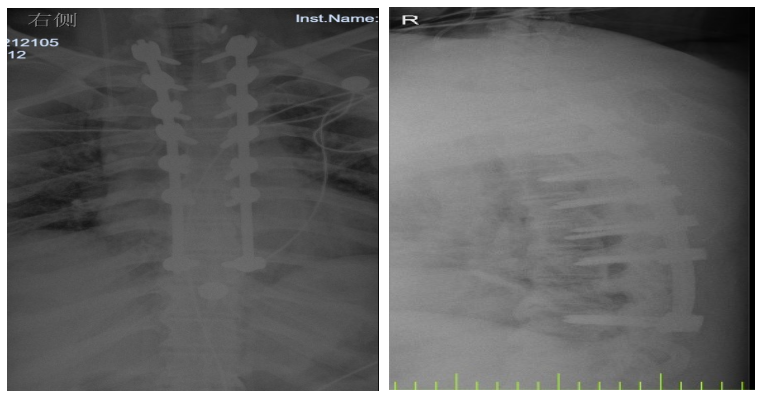

入院后,國文醫(yī)院骨科迅速組織多名專家會診,并為吳先生完善了頸椎及胸椎的 MRI 檢查。結果顯示,吳先生的頸椎及胸椎多階段嚴重椎管狹窄,脊髓壓迫超過 50%,情況十分危急。經過骨科專家團隊的綜合會診及評估,最終為他制定了一套個性化的治療方案,包括頸椎后路單開門椎管減壓頸椎融合內固定術,以及胸椎間盤切除伴椎管減壓胸椎植骨融合內固定術。在完善術前檢查、確認無手術禁忌后,骨科主任呂國福如期為吳先生實施了手術。

手術涉及頸椎及胸椎多個階段,操作難度極大。專家團隊采用 “蠶食法” 減壓,分塊去除增生韌帶,最大程度減少對脊髓的損傷;同時運用椎弓根螺釘固定技術,確保手術部位的穩(wěn)定性。

術后 3 天,吳先生的下肢肌力就從 3 級恢復到了 4 級;術后 1 個月,胸部束縛感明顯緩解;術后 3 個月,他已經能夠重返工作崗位,生活基本恢復正常。